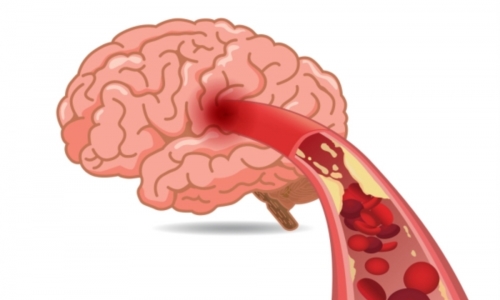

뇌경색 원인은 동맥경화증으로 시작합니다. 병이 든 혈관 어떤 곳에든 핏덩어리가 생겨나면 심장에서 뇌로 흐르는 혈액의 흐름을 방해하게 됩니다. 만약 핏덩어리가 내경동맥이나 뇌혈관을 막게 되면 치명적인 뇌 손상을 입을 수 있습니다. 이렇듯 갑자기 혈관을 막는 경우도 있으나, 혈전에 의하여 점차 혈관 너비가 좁아지면서 허혈성 뇌졸중이 유발되는 경우도 있습니다.